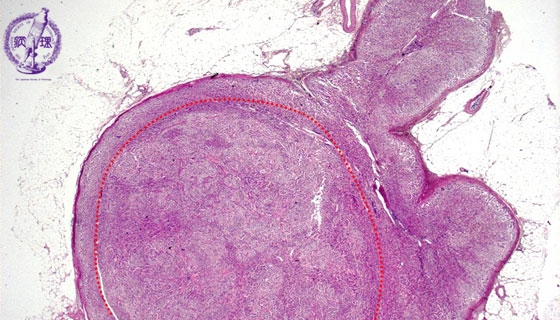

Microscopic findings (HE stain, low power view). The nodule (dotted line) located in adrenal cortex. The boundary between the nodule and normal adrenal cortex is unclear.